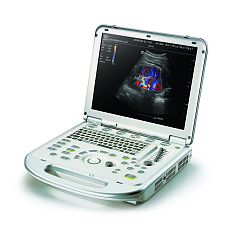

Клинические изображения

- Широкий спектр клинических приложений для неотложной помощи

Благодаря широкому набору датчиков и функций система Sparq подходит для самых разных категорий исследований и создает изображения отличного качества для пациентов почти любого телосложения. Поддерживаемые исследования: ЭхоКГ и чреспищеводная ЭхоКГ, легкие, сосудистый доступ, органы брюшной полости, скелетно-мышечная система, FAST, нервы, глаза, поверхностно расположенные органы и органы малого таза.